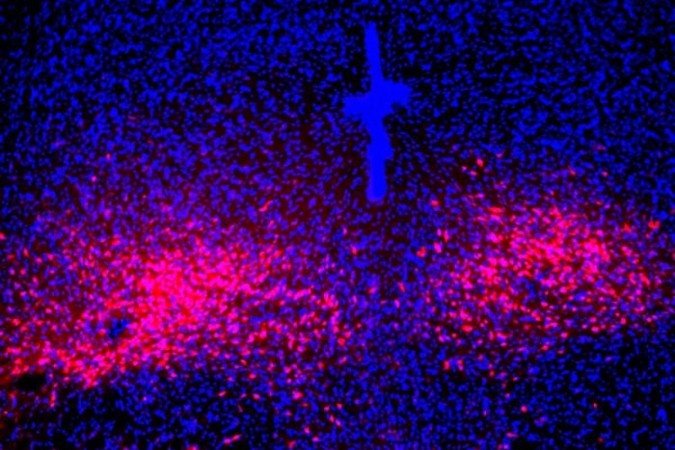

• Peptídeos PACAP expressos (vermelho) no cérebro de ratos com modelo de síndrome do pânico

Peptídeos PACAP expressos (vermelho) no cérebro de ratos com modelo de síndrome do pânico Foto: Instituto Salk/Divulgação

Os cientistas constataram que, durante um ataque de pânico, os neurônios que expressam a proteína foram ativados. Quando isso acontece, eles liberam o neuropeptídeo mensageiro Pacap para outra parte do cérebro chamada rafe dorsal, onde residem os neurônios que expressam os receptores da proteína. Então, são produzidos os sintomas comportamentais e físicos associados ao transtorno.